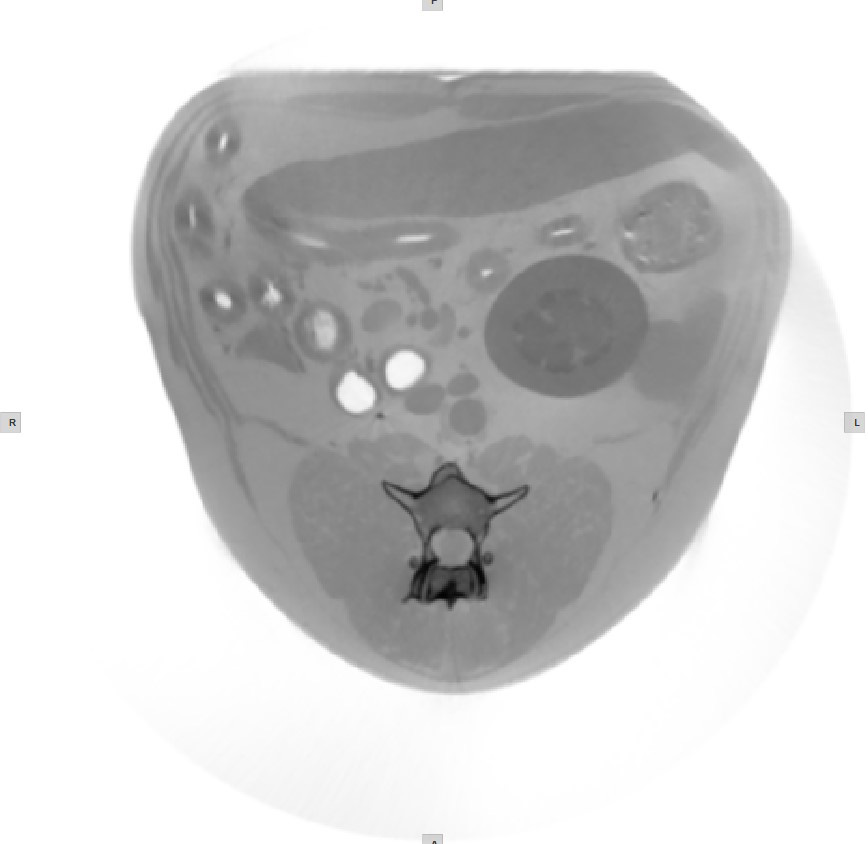

Histogram¶

A windowing histogram is a graphical representation of the distribution of intensity values in an image. It displays the number of pixels at each intensity level, allowing users to adjust the brightness and contrast by setting a window around a range of intensity levels. By adjusting the position and width of the window, the user can optimize the image for their specific needs and better visualize the image features.

To change the window width, press and drag the left or right edge of the rectangular area representing the window.

To change the position or the window center, press and hold on the rectangular area and drag in the desired direction.

Invert Image¶

The process of inverting the dark pixels into light pixels and vice versa in an image based on the DICOM standard is called inverting the polarity of the image.